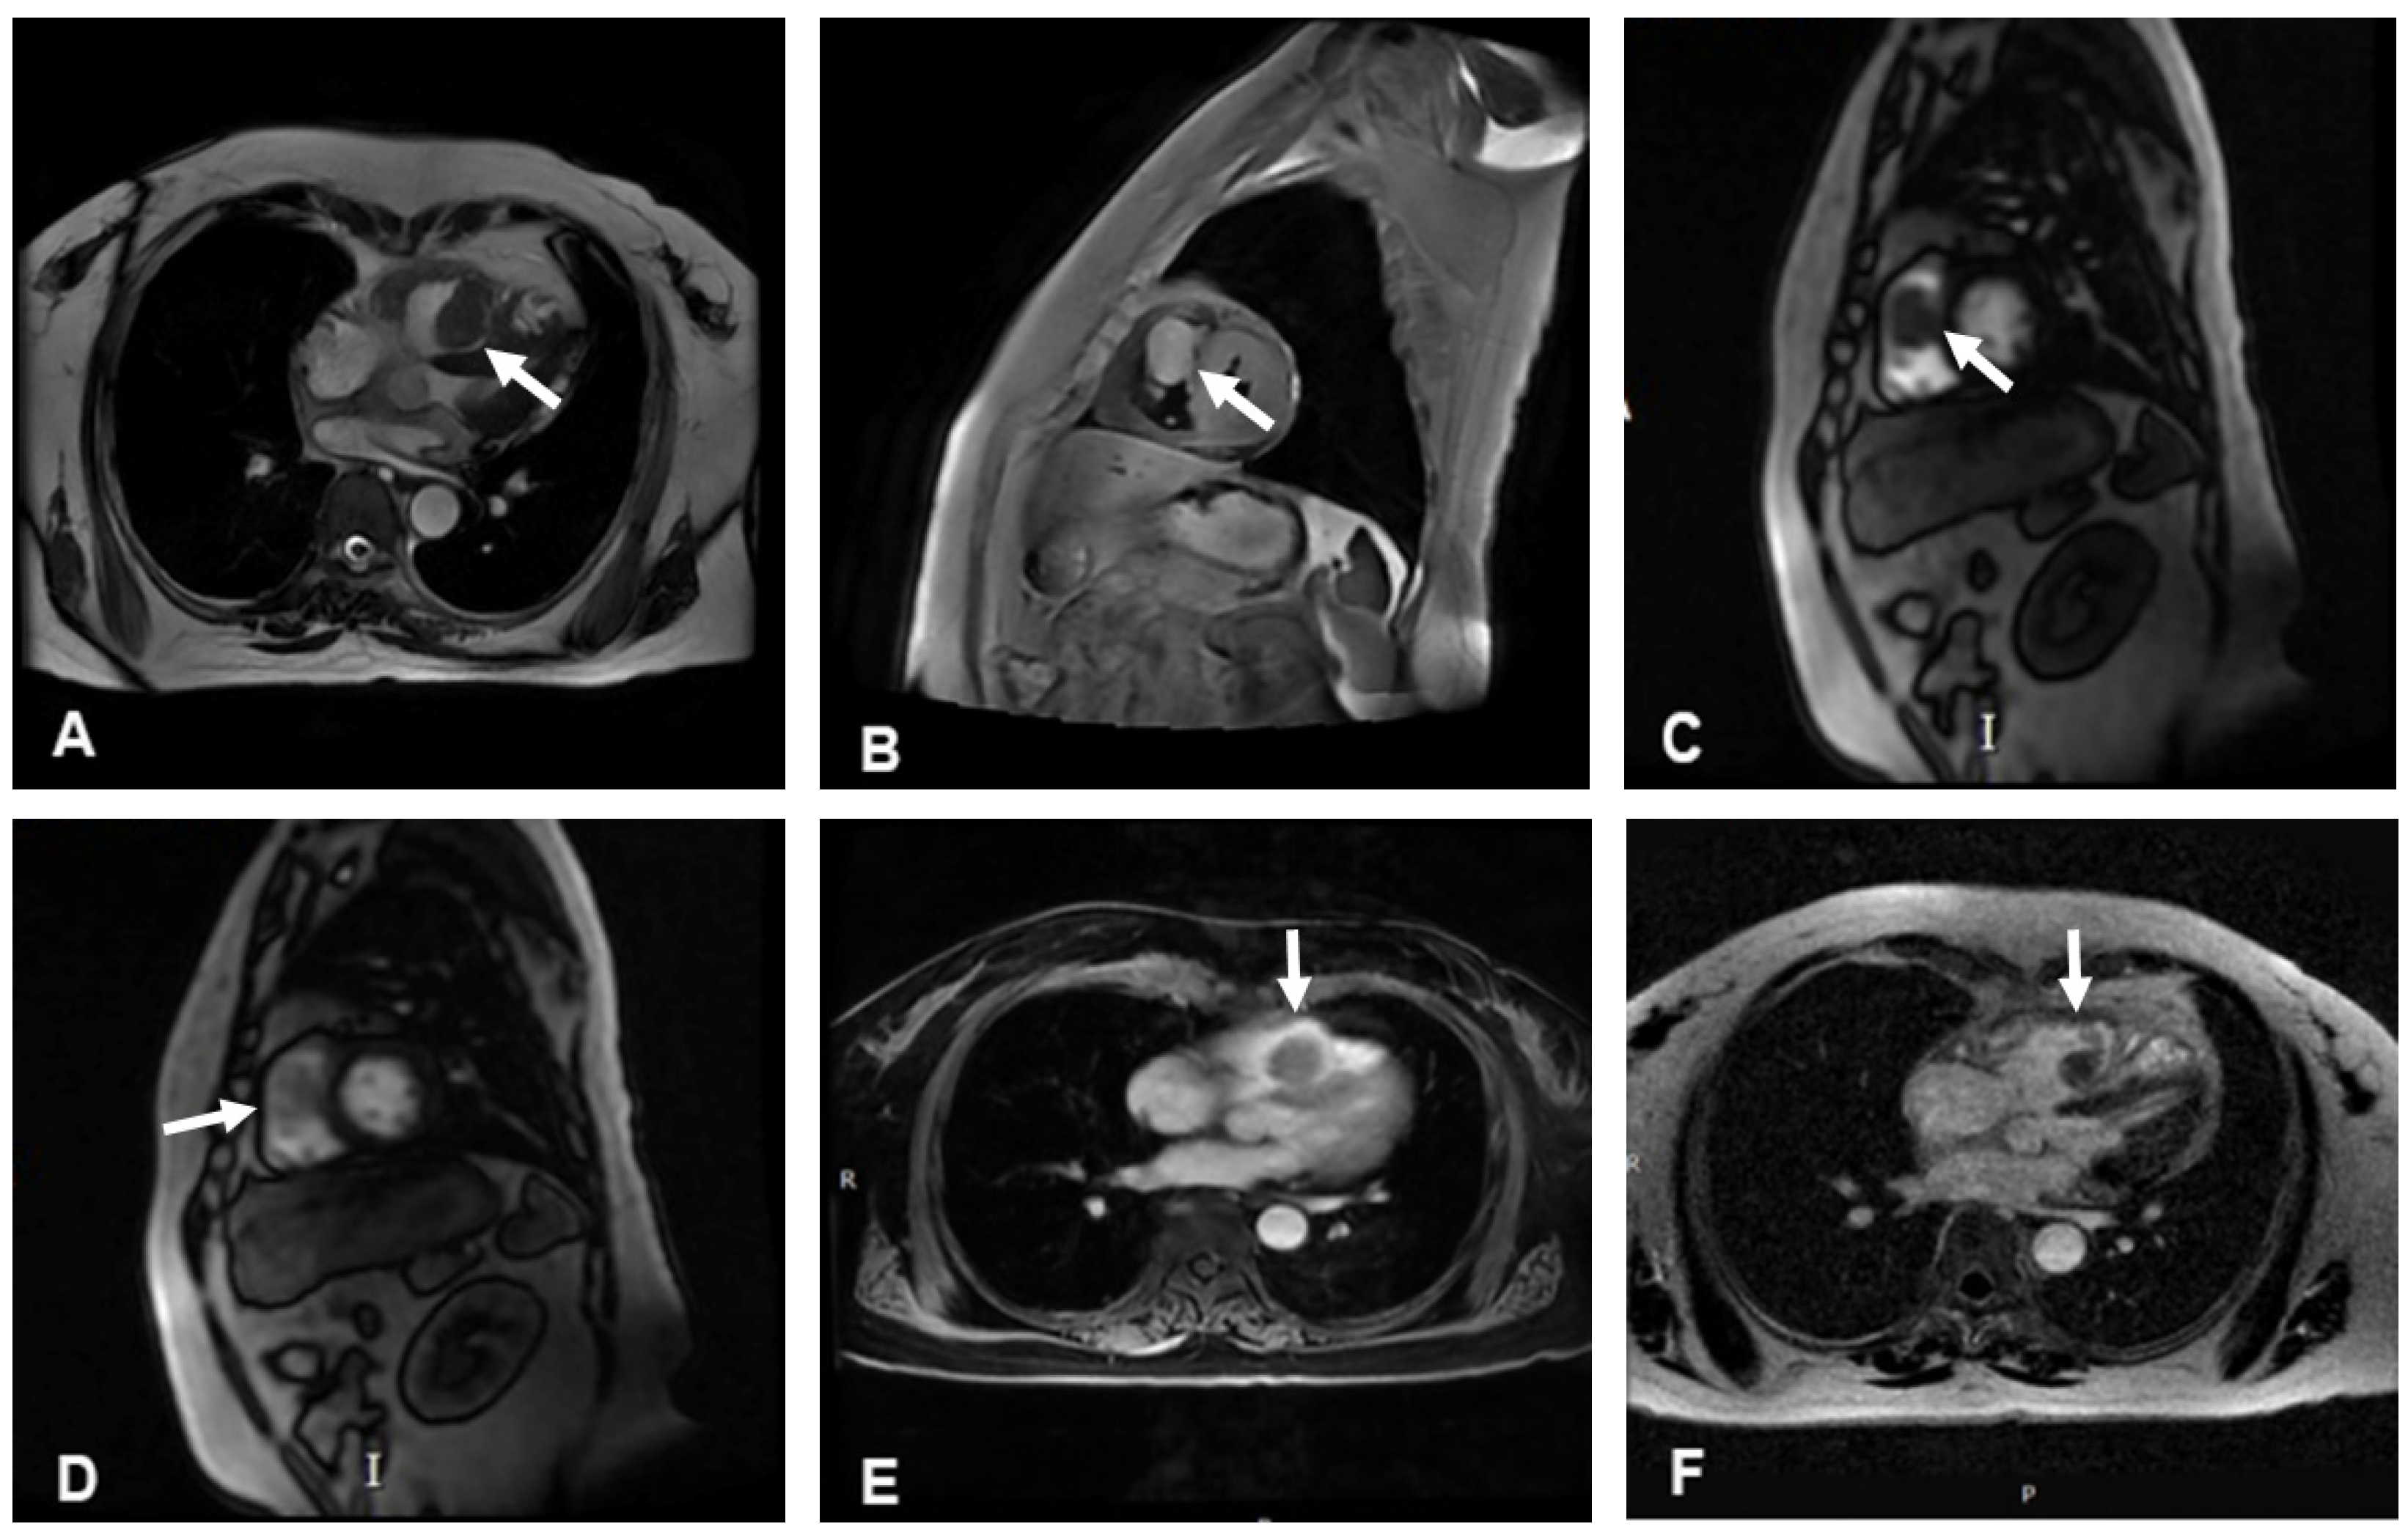

The cine cardiac magnetic resonance (CMR) images showed a hypointense mass with regular contours, which adhered to the interventricular septum and protruded into the right ventricular cavity. The signal intensity of the mass was high on T2-weighted images, without any signal decrease on the fat suppression sequence. However, pericardial or pleural effusion was not observed. CMR rest perfusion sequences demonstrated a rapid signal increase in the mass following an augmentation in the left ventricular blood pool signal, which implied that the mass was perfused by the aorta, and then a rapid decrease in signal intensity on early gadolinium enhancement (Figure 3). Moreover, myocardial delayed gadolinium enhancement was considerably lower than the blood pool signal at the same level.

Figure 3.

Cardiac magnetic resonance imaging. (A) Cine images of magnetic resonance imaging showed a hypointense mass. (B) The signal intensity of the mass was high on T2-weighted images. (C,D) The mass showed a rapid enhancement on CMR rest perfusion. (E) The signal intensity of the mass decreased rapidly on early gadolinium enhancement. (F) Myocardial delayed gadolinium enhancement was significantly lower than the blood pool signal at the same level. White arrows indicate the location of the mass in each image.